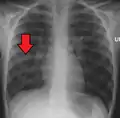

![]() | |

| Chest X-ray of a pneumonia caused by influenza and Haemophilus influenzae, with patchy consolidations, mainly in the right upper lobe (arrow) | |